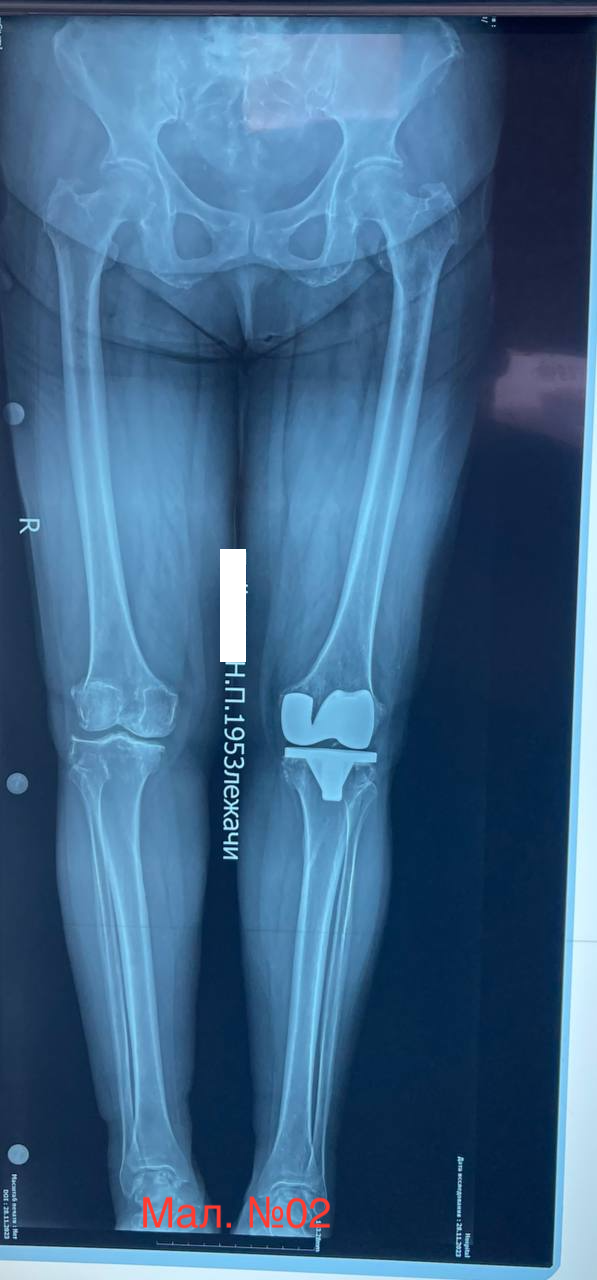

photo_2023-12-13 17.20.43